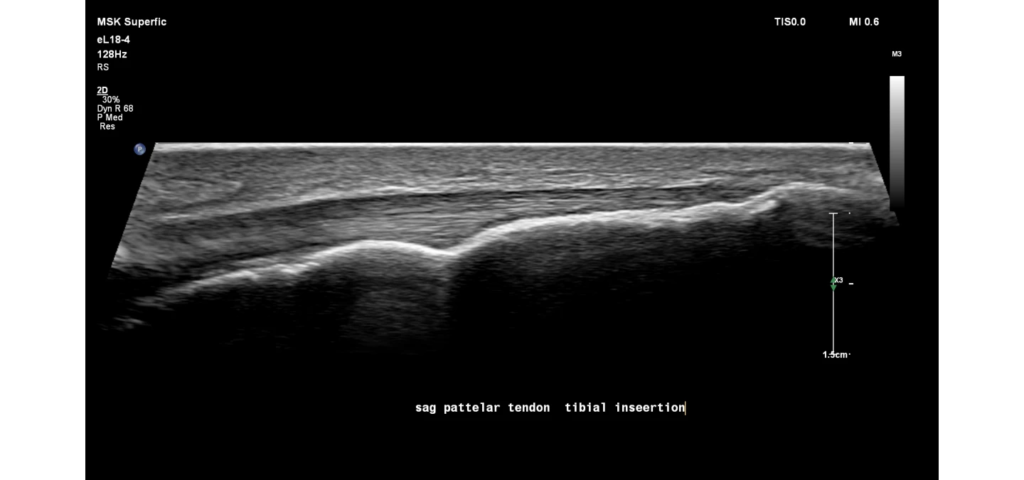

Philips EPIQ Elite ultrasound features an exceptional level of clinical performance, workflow, and advanced intelligence to meet the challenges of today’s most demanding practices. The EPIQ Elite platform brings ultimate solutions to ultrasound, with clinically tailored tools designed to elevate diagnostic confidence to new levels.